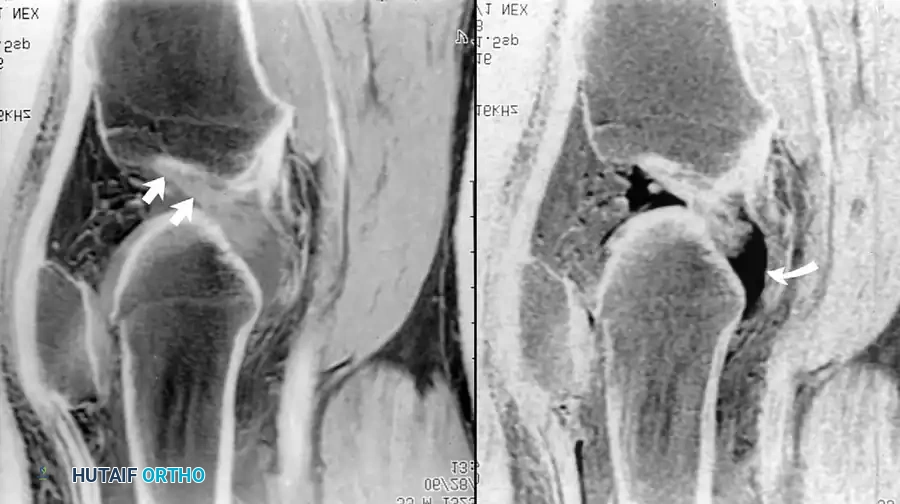

علاج عيوب الغضروف المفصلي والعظام

في حالات التهاب العظم والغضروف السالخ، يتدخل الجراح عندما يظهر الرنين المغناطيسي وجود سوائل خلف القطعة العظمية مما يدل على عدم استقرارها. تتراوح الخيارات الجراحية بين التثقيب بالمنظار لتحفيز النخاع العظمي على الشفاء، إلى تثبيت القطعة المنفصلة، أو زراعة غضروف ذاتي في حالات العيوب الكبيرة.